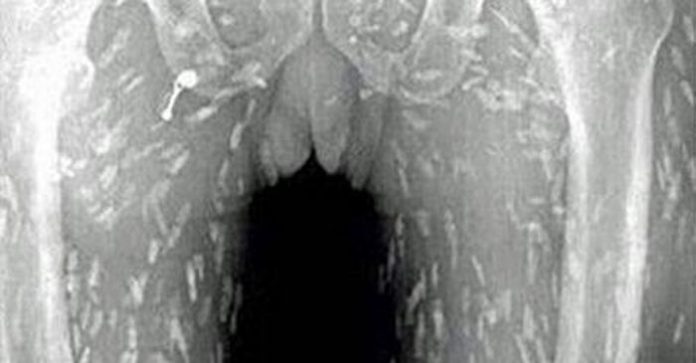

Все началось с обычной боли в животе и зуда кожи. Мужчина пошел к врачу, ему сделали снимки – и вот он ужас! Все его тело было поражено солитерами. Причина? Чрезмерное потребление сырых кусочков рыбы, известных как «сашими».

Сначала была обычная боль в животе и зуд кожи. Он обратился к врачу, ему сделали рентгеновские снимки и обнаружили нечто ужасное: все тело было поражено паразитами. Причина? Чрезмерное употребление сырых кусочков рыбы!

Основной причиной подобной ситуации явилось то, что часть этой сырой рыбы оказалась зараженной. К такому выводу пришло специалисты Народного госпиталя Гуанчжоу, провинция Гуандун.